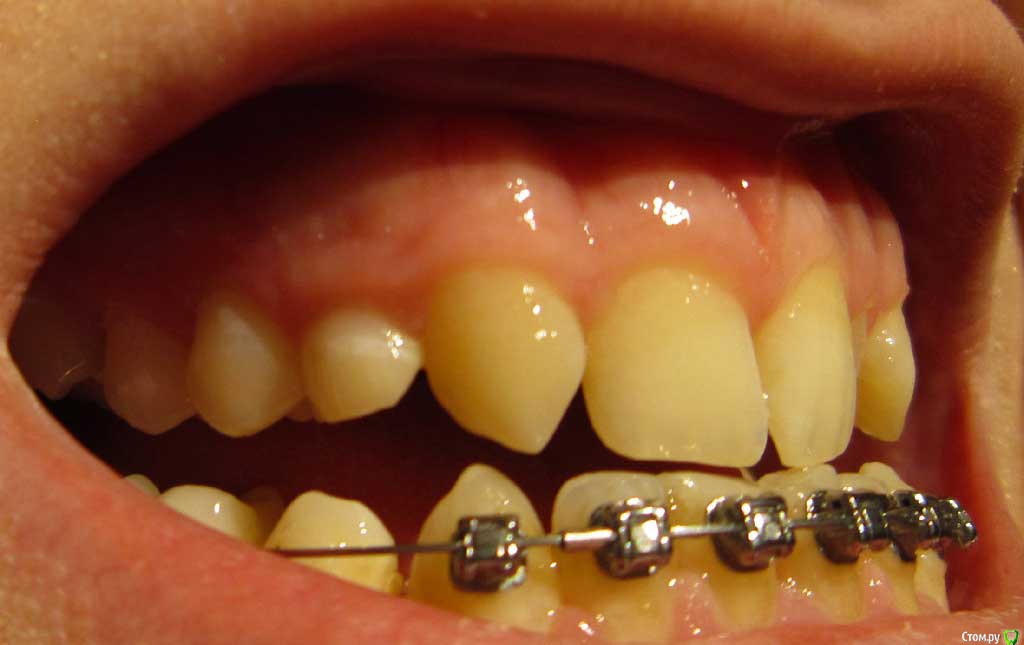

Сейчас мне 17 лет. На лечении у ортодонта с августа 2013 года. Удалили молочные пятерки и стали сдвигать шестерки к передним зубам. На верхнюю челюсть она ставить брекеты не стала. Осенью 14 года врач ушла в декрет.

Пришел новый врач который предложил все сделать несколько иначе: поставить брекеты на обе челюсти, все выравнять и освободить место под будущие импланты: вместо пятерок снизу и второго слева резца сверху -, а пока на их место поставить коронки. Также врач назвал сроки: около 1 года.

Сверху слева отсутствует зачаток второго резца, вместо него находится клык и молочный зуб левее. Внизу нет зачатков пятерок.